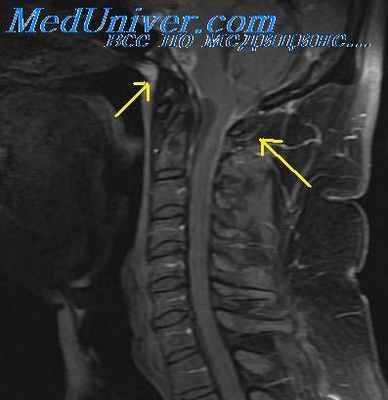

В настоящее время основными инструментальными методами диагностики абсцесса головного мозга являются МРТ и КТ, которые обладают высокой разрешающей способностью в отношении определения локализации, размеров и структуры абсцесса, например плотности его капсулы или содержимого его полости. При отсутствии этих методов применяют обзорное и томографическое рентгенологическое исследование черепа и головного мозга, рентгенографию височных костей по Шюллеру, Майеру и Стенверсу, а также некоторые аксиальные проекции, позволяющие оценить состояние базальных отделов черепа и головного мозга. Возможно применение и других методов исследования головного мозга, таких как ЭЭГ, УЗ-диагностика, реоэнцефалография, ангиография, вентрикулография, однако с введением в практику МРТ и КТ эти методы сохранили за собой лишь вспомогательные функции.

МРТ головного мозга в T2 режиме демонстрирует скопление спинномозговой жидкости в конвекситальном пространстве при церебральном арахноидите (указано стрелками).